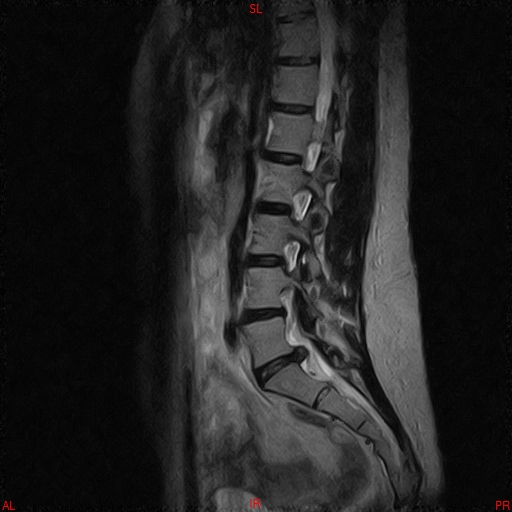

• Resonancia PATOLÓGICA DE C.LUMBAR - HERNIA DE DISCO L5-S1 -  SAG T2